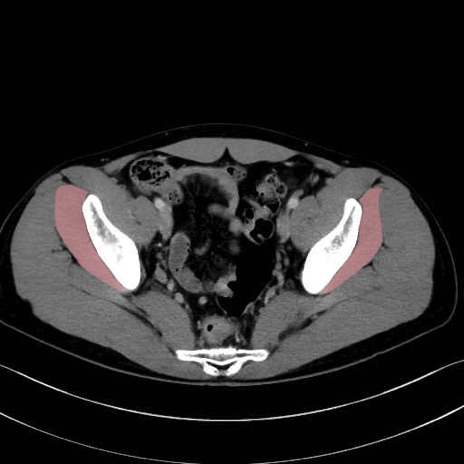

小殿筋 (Gluteus minimus)